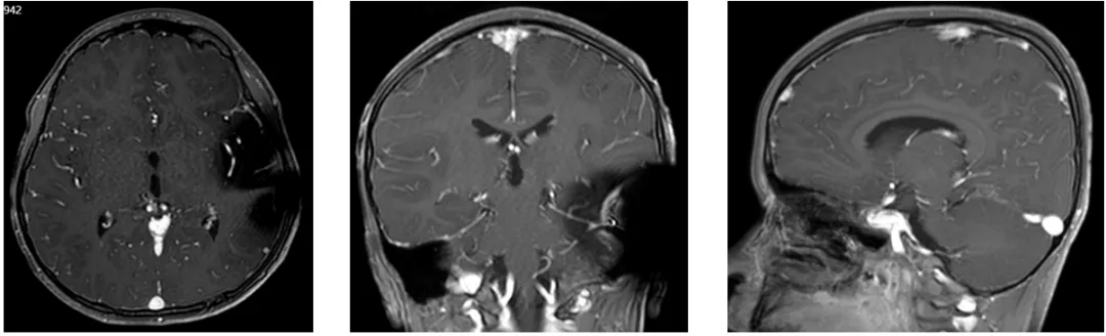

2024年1-2行全中枢放疗,期间共放疗30次,2024年3月放疗结束后复查MR影像提示病灶较前明显缩小,双侧脑室积液较前减轻。(图9)。

图9放疗结束后复查MR影像